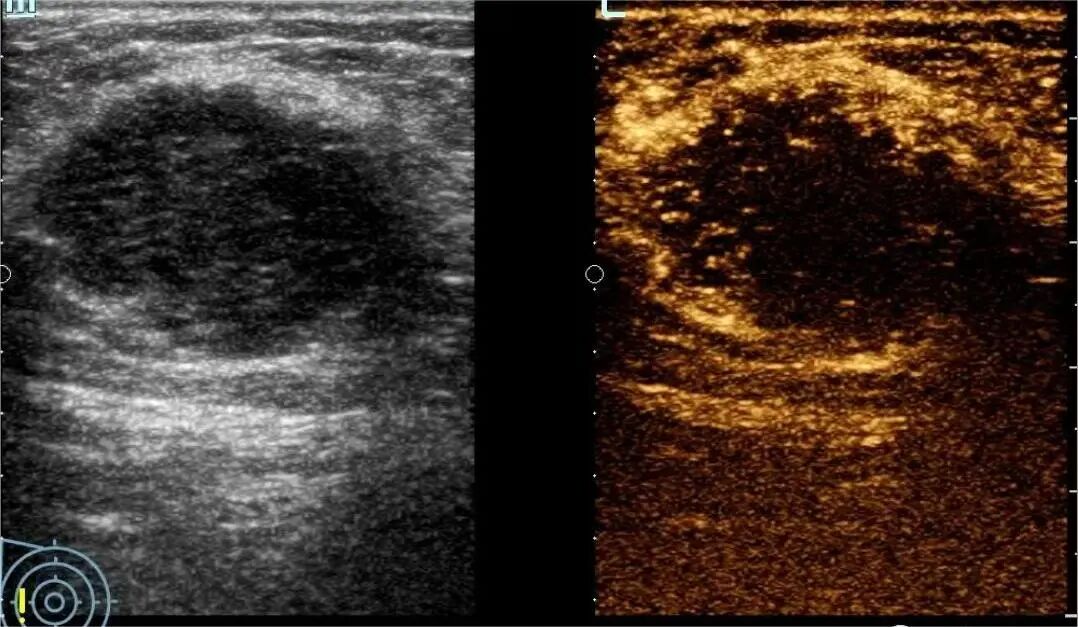

您是否也遇到过这些尴尬时刻?提重物时突然漏尿、运动时总觉下腹坠胀、更年期后总想跑厕所......这些信号可能在提醒:盆底肌需要关爱了。 盆底肌群如同"弹簧床",承托着膀胱、子宫等器官。妊娠分娩、雌激素变化、长期腹压增加等因素,都可能导致这张"网"松弛。若不及时干预,可能发展为: ▷ 盆腔器官脱垂(子宫/阴道膨出) ▷ 压力性尿失禁(咳嗽/大笑漏尿) ▷ 排便障碍(便秘/失禁) ▷ 性生活质量下降 【哪些人需要关注盆底筛查?】 ✓ 产后42天妈妈(尤其经阴道分娩) ✓ 频繁漏尿或排尿困难 ✓ 长期便秘/慢性咳嗽 ✓ 更年期女性 ✓ 性生活疼痛或下腹坠胀人群 【无创筛查新选择:盆底超声】 不同于传统指检,这项技术通过会阴体表扫描: ⏩ 多维度观察静息/收缩/用力状态 ⏩ 精准评估肌群损伤程度 ⏩ 动态捕捉器官位移情况 女性盆底三维多层显像 【检查须知】 ✔️ 避开经期 ✔️ 检查前排空膀胱 ✔️ 穿宽松裤装更方便 ✔️ 配合医生指令做缩肛/屏气动作 盆底超声检查 女性健康管理不该止于体检常规项。建议存在相关症状的女性,及时到正规医院妇产科或超声科咨询。早筛查、早干预,让盆底肌恢复应有的"托举力"。 注:部分图片来源于网络,如有侵权,请联系删除。 贵州航天医院超声科专家团队 吴艳辉 中共党员,超声科学科带头人、主任,主任医师 专业擅长:从事超声诊断工作约30年,对心血管、小器官超声、超声引导下介入等具有丰富的临床经验。 胡大海 超声科副主任,副主任医师 专业擅长:从事超声工作17年,对心血管、外周血管、浅表器官超声诊断等具有丰富的临床经验。 骆科美 中共党员,超声科副主任医师 专业擅长:从事超声诊断工作33年,对胎儿心脏及颅脑、妇产超声诊断、盆底超声等诊断具有丰富的临床经验。 刘 敏 超声科副主任医师 专业擅长:从事超声诊断工作20余年,对妇产科超声、心脏血管超声诊断具有丰富的临床经验。 贵州航天医院超声科简介 基本情况 贵州航天医院超声科配备多种超声检查设备(飞利浦彩超(IU-22、IU-Elite、HD11、Q5、Q7),迈瑞超声I9、DC-6、DC-8、GE-E8及床旁机,彩色超声诊断仪等),设有心血管诊室、妇产科诊室、腹部诊室、绿色通道、浅表小器官等检查室。 诊疗范围 科室业务覆盖腹部、泌尿、妇科、产科(常规、NT筛查、III级筛查超声检查及高危妊娠监护)、成人心脏、外周血管、浅表器官(包含甲状腺、乳腺、阴囊、眼睛等)、颅脑(小儿颅脑、成人颅脑)、小儿肺超、造影、盆底、腹直肌、肌骨神经等检查及各种介入引导。 专科特色 四肢血管超声检查、双胎产前筛查及超声监护、超声造影检查技术、介入超声临床应用、经颅脑实质超声辅助筛查诊断帕金森病、女性性早熟超声诊断、盆底超声检查等。 NT超声检查 超声介入引导 肝脏超声造影 甲状腺造影 颅脑超声帕金森辅助检查 乳腺超声造影 上肢动静脉造瘘超声检查 双胎超声筛查 下肢血管超声检查 右心造影 END